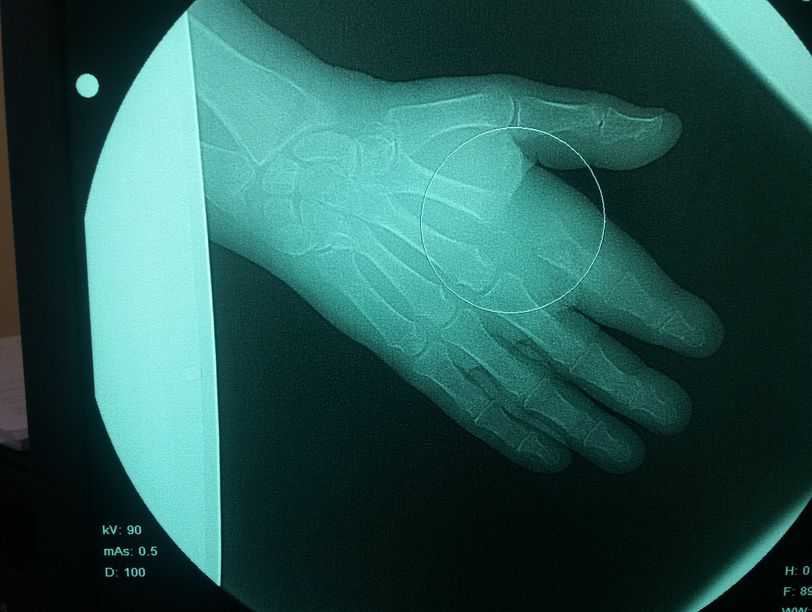

It.s ostemyelitis

Osteomyelitis